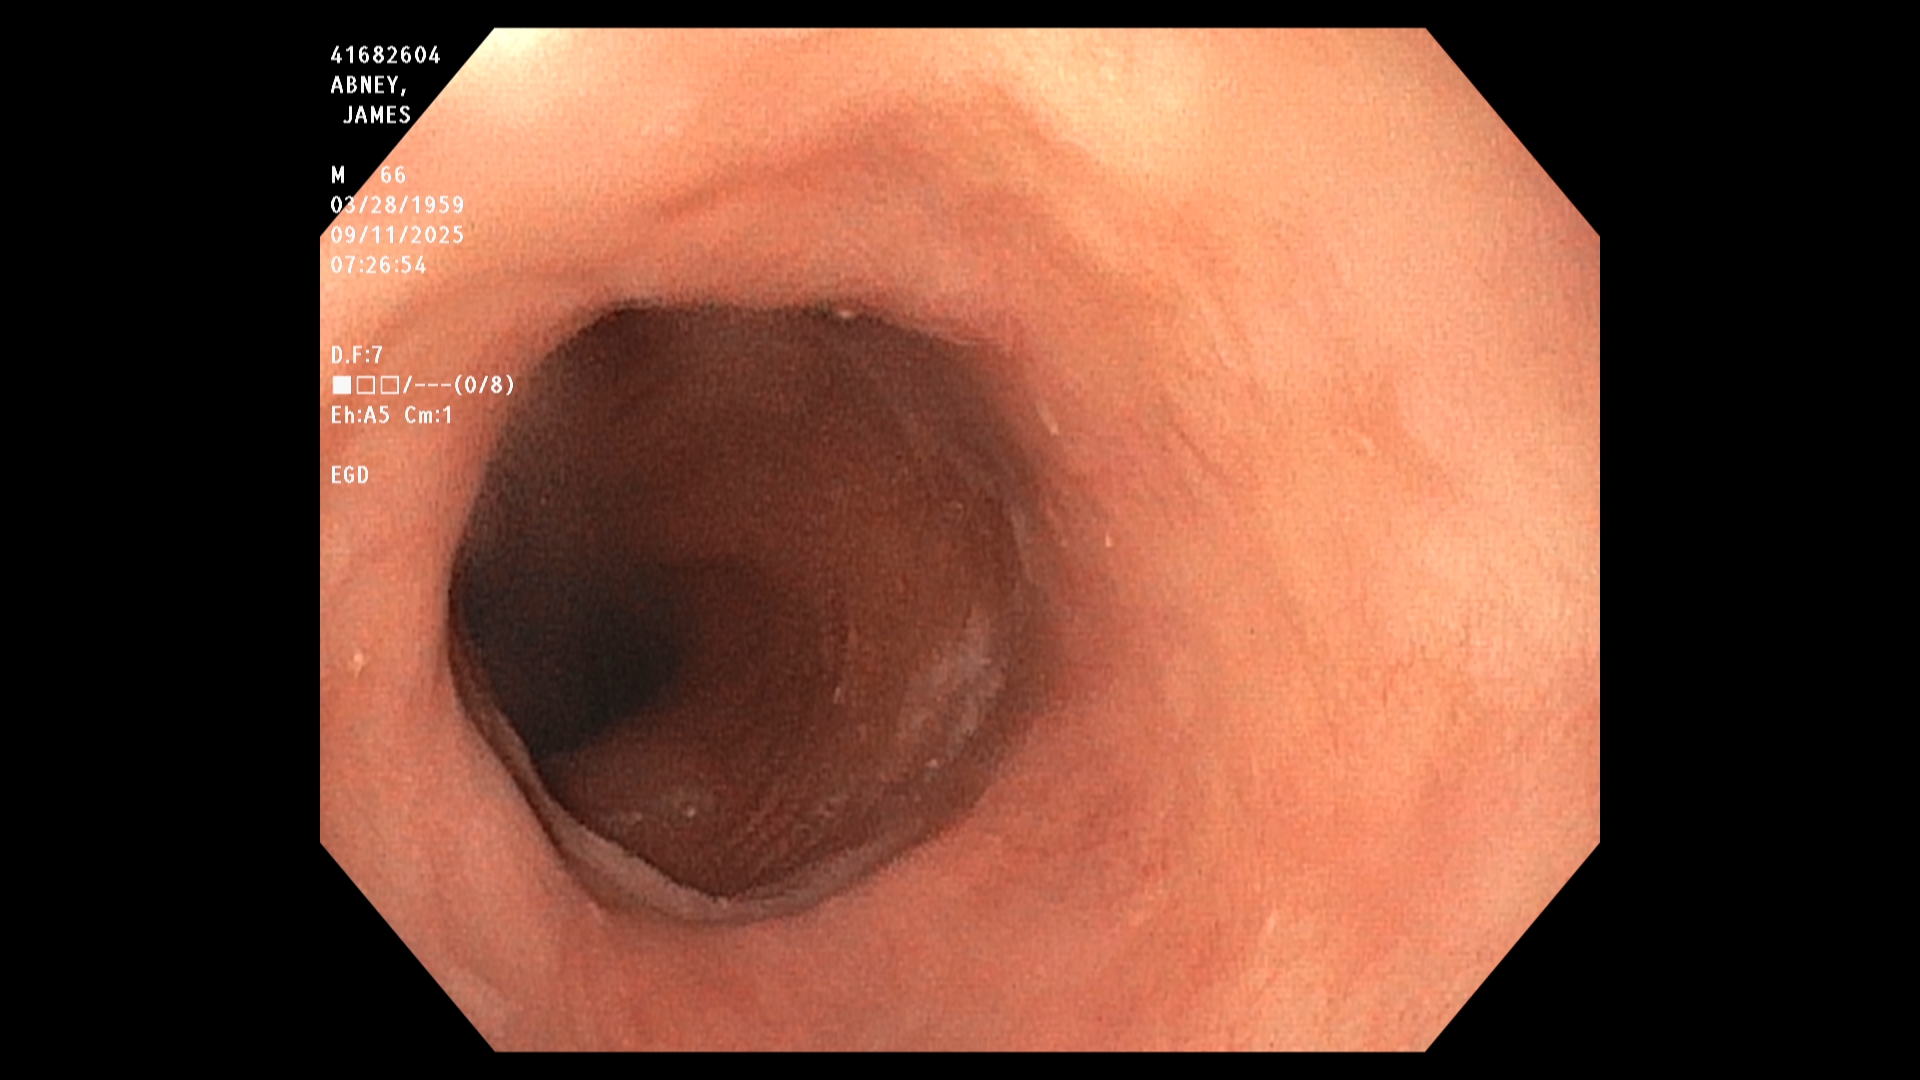

The endoscopist in this study generated a series of images showing the stomach, duodenum,

duodenal bulb, and esophagus, among others. The stomach was imaged first. The image is a

retroflexed view, in which the endoscope was passed through the stomach and the camera

turned backward to take the image, which shows both the stomach and an upstream portion of

the endoscope. The endoscope was next passed into the duodenum, farther down the GI tract,

and then withdrawn while care was taken to observe mucosal detail.

The EGD results in this study were good. In particular, the endoscopist stated that all observed

structures appeared normal and that there was no evidence of any damage, including acid-

reflux damage.